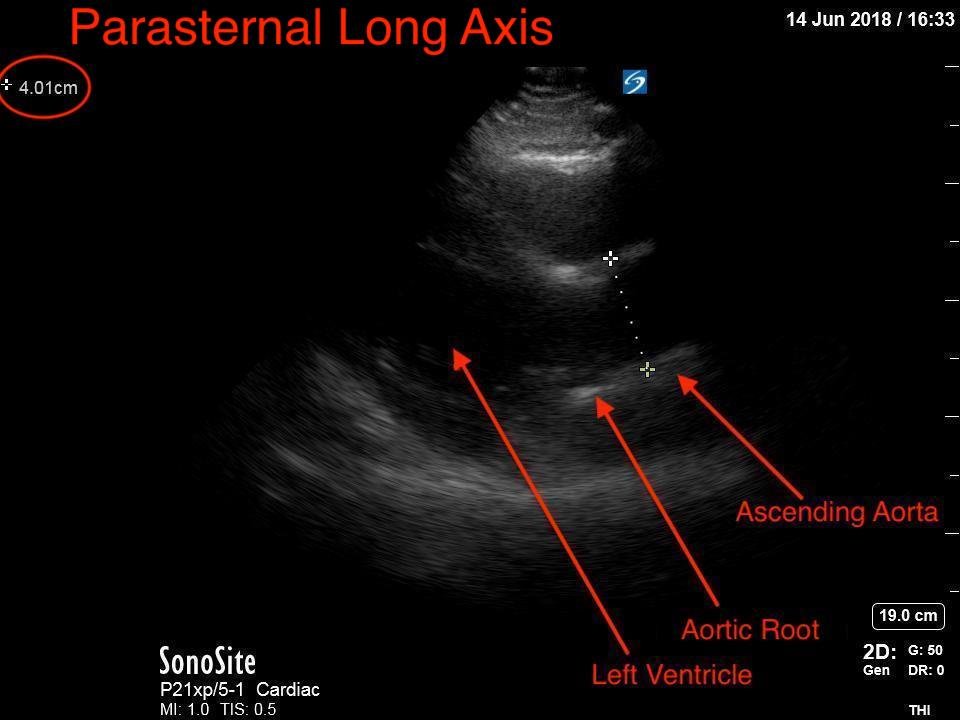

Point-of-care cardiac echocardiogram demonstrated a dilated ascending aorta (illustrated in red) measuring approximately 4 cm in the parasternal long axis (PLAX). A dilated aortic arch (illustrated in green) also measuring approximately 4 cm was appreciated using the suprasternal notch view (SSNV). A follow-up computed tomography angiogram (CTA) was performed, validating bedside ultrasound measurements.

The diagnostic criteria for dilated thoracic aneurysm is based on multiple factors including age, sex, and body size.2 An aortic root diameter of ³ 4.0 cm constitutes an ascending aortic dilation.3,4 Point-of-care cardiac and SSNV ultrasound of the thoracic aorta has been validated as an accurate study when performed by emergency physicians to identify thoracic aortic aneurysms (sensitivity of 71.4%, specificity of 100% when compared to gold standard of CTA). 5 This case is an example of the utility of rapid bedside diagnostic ultrasound, specifically the SSNV, in assessment of thoracic aneurysms.

Point-of-care cardiac echocardiography demonstrated a dilated ascending aorta. Finding a new thoracic aortic aneurysm in the setting of chest pain and hypertension is a “can’t miss” diagnosis due to the potential for rapid expansion leading to dissection and/or rupture.6 Point-of-care ultrasound utilizing the SSNV is a tool that can be used early in the evaluation of the patient that can help make quick determination of diagnostic plan and expedite initiating treatment in the emergency department.